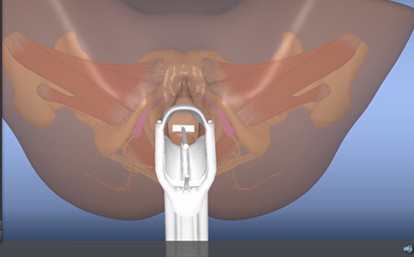

As a strong didactic tool, the PELVIC Mentor provides trainees with immediate feedback on anatomical recognition and the opportunity to practice pelvic exams accurately. The unique combination of the model’s anatomical structure, finger sensation and virtual model provide the most effective training tool to date, aimed at developing the physician’s confidence during pelvic examinations.

Features and Benefits

- Practice on pathologies not found with standardized patients and other simulators